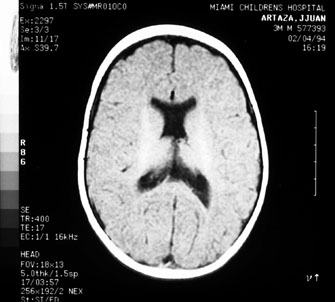

Prognosis for recovery depends on etiology, age of onset, and severity of brain damage (Fig. 7). Although such children often remain visually handicapped, dramatic recovery may ensue occasionally.36 Cortical visual loss from perinatal hypoxia/ischemia has a particularly poor prognosis if congenital, but up to a 70% recovery rate if acquired.37 Although hydrocephalus, brain dysgenesis, and infections may produce cortical visual loss, by far the most common cause of CVI in the developed world is perinatal hypoxia. In term infants, damage primarily affects the watershed areas of the cerebral cortex (frontal and parieto-occipital regions). In premature babies, however, the damage is predominantly periventricular. Age-related differences in the developing intracranial vascular systems may account for the disparate sites of injury. The watershed zone in term infants (and adults) is at the parieto-occipital junction, whereas in preterm infants it is in the subcortical area.38

Fig. 7. Computed tomography of child with cortical visual impairment resulting from congenital hydrocephalus. Note significant ex vacuo dilatation of the ventricles posteriorly, with shunt catheter in place.